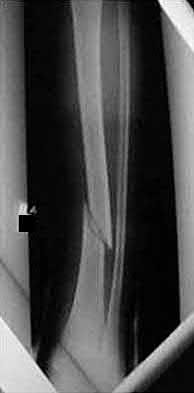

2. # A 35-year-old woman is involved in a head-on collision while driving. Initial radiographs are shown in Figures 8a and 8b. Injury to what vessel increases the risk for osteonecrosis of the injured bone?

5. Artery of the tarsal sinus Corrent answer: 4

The patient has a Hawkins type III talar neck fracture-dislocation with a risk of osteonecrosis ranging from 69% to 100%. Anatomic studies have shown that the artery of the tarsal canal supplies the lateral two thirds of the talar body.

The other vessels listed provide no significant contribution to the talus.